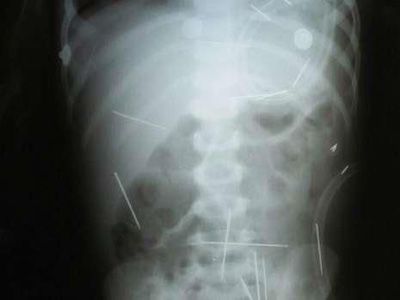

由于男童的身体表面没有任何明显的外伤,当地医生查不出男童腹痛的原因,所以最后只好为他拍摄了X光照片,结果X光照片出来后,将医生们全都惊得目瞪口呆。原来X光照片显示,这名男童的体内竟然到处都是横七竖八的缝衣针, 一些针甚至长达5厘米!医生仔细数了一下,发现在这名男童的腹部、脖子部位、胸膛部位、大腿上以及消化系统中,竟总共隐藏着50根缝衣针,其中一根缝衣针还戳进了男童的左肺中!由于这些缝衣针大多不在男童的消化系统内,所以它们显然不是被男童误吞进体内、而是被人蓄意一根根地戳进他的皮肤中的。